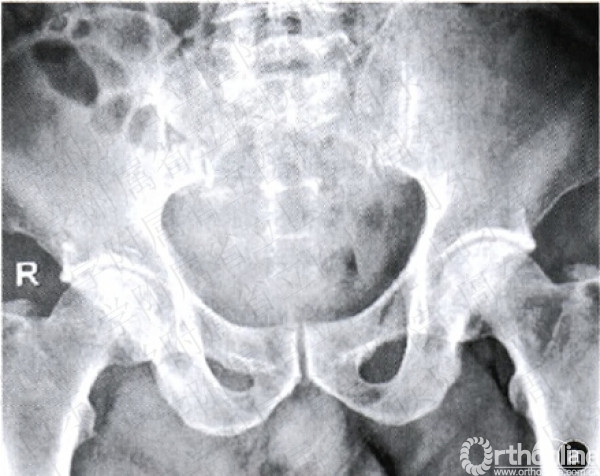

图2造影栓塞术止血手术及示意图a骨盆正位x线片示Tile分型A型骨盆骨折b动脉造影示意图示左侧髂内动脉的一个分支出现“冒烟”征,证明有动脉的活动性出血e行髂内动脉造影术示髂内动脉分支出血,典型的“冒烟”症,A为髂总动脉,B髂外动脉,c髂内动脉,箭头示出血点d示意图示注入明胶海绵.等栓塞材料行髂内动脉栓塞,栓塞后再次造影检查示动脉出血征象消失e行墨多髂内动脉栓塞术,再次造影示出血停止,箭头示髂内动脉栓塞部位

2.栓塞组:局麻后,患者取仰卧位,采用Seldinger法行股动脉穿刺插管(用带芯穿刺针穿透血管,拔出针芯,缓慢向外退针,至血液从针尾喷出,迅速插入导针后,拔出穿刺针,通过导丝引入导管至股动脉)。将5~7F猪尾导管置于腹主动脉分叉上2—3cm,注入对比剂造影,而后更换Cobra导管选择性地行髂内动脉造影,此时可发现动脉出血部位造影剂外渗,形成“冒烟”征(图2a~2c)。选择髂内动脉主干或分支动脉注入明胶海绵颗粒进行栓塞,再次造影复查,如出血征象消失则停止注入栓塞剂(图2d,2e)。栓塞组12例行髂内动脉主干栓塞,1例行骶正中动脉栓塞,4例行髂内动脉分支血管栓塞(闭孔动脉1例,臀上动脉3例)。